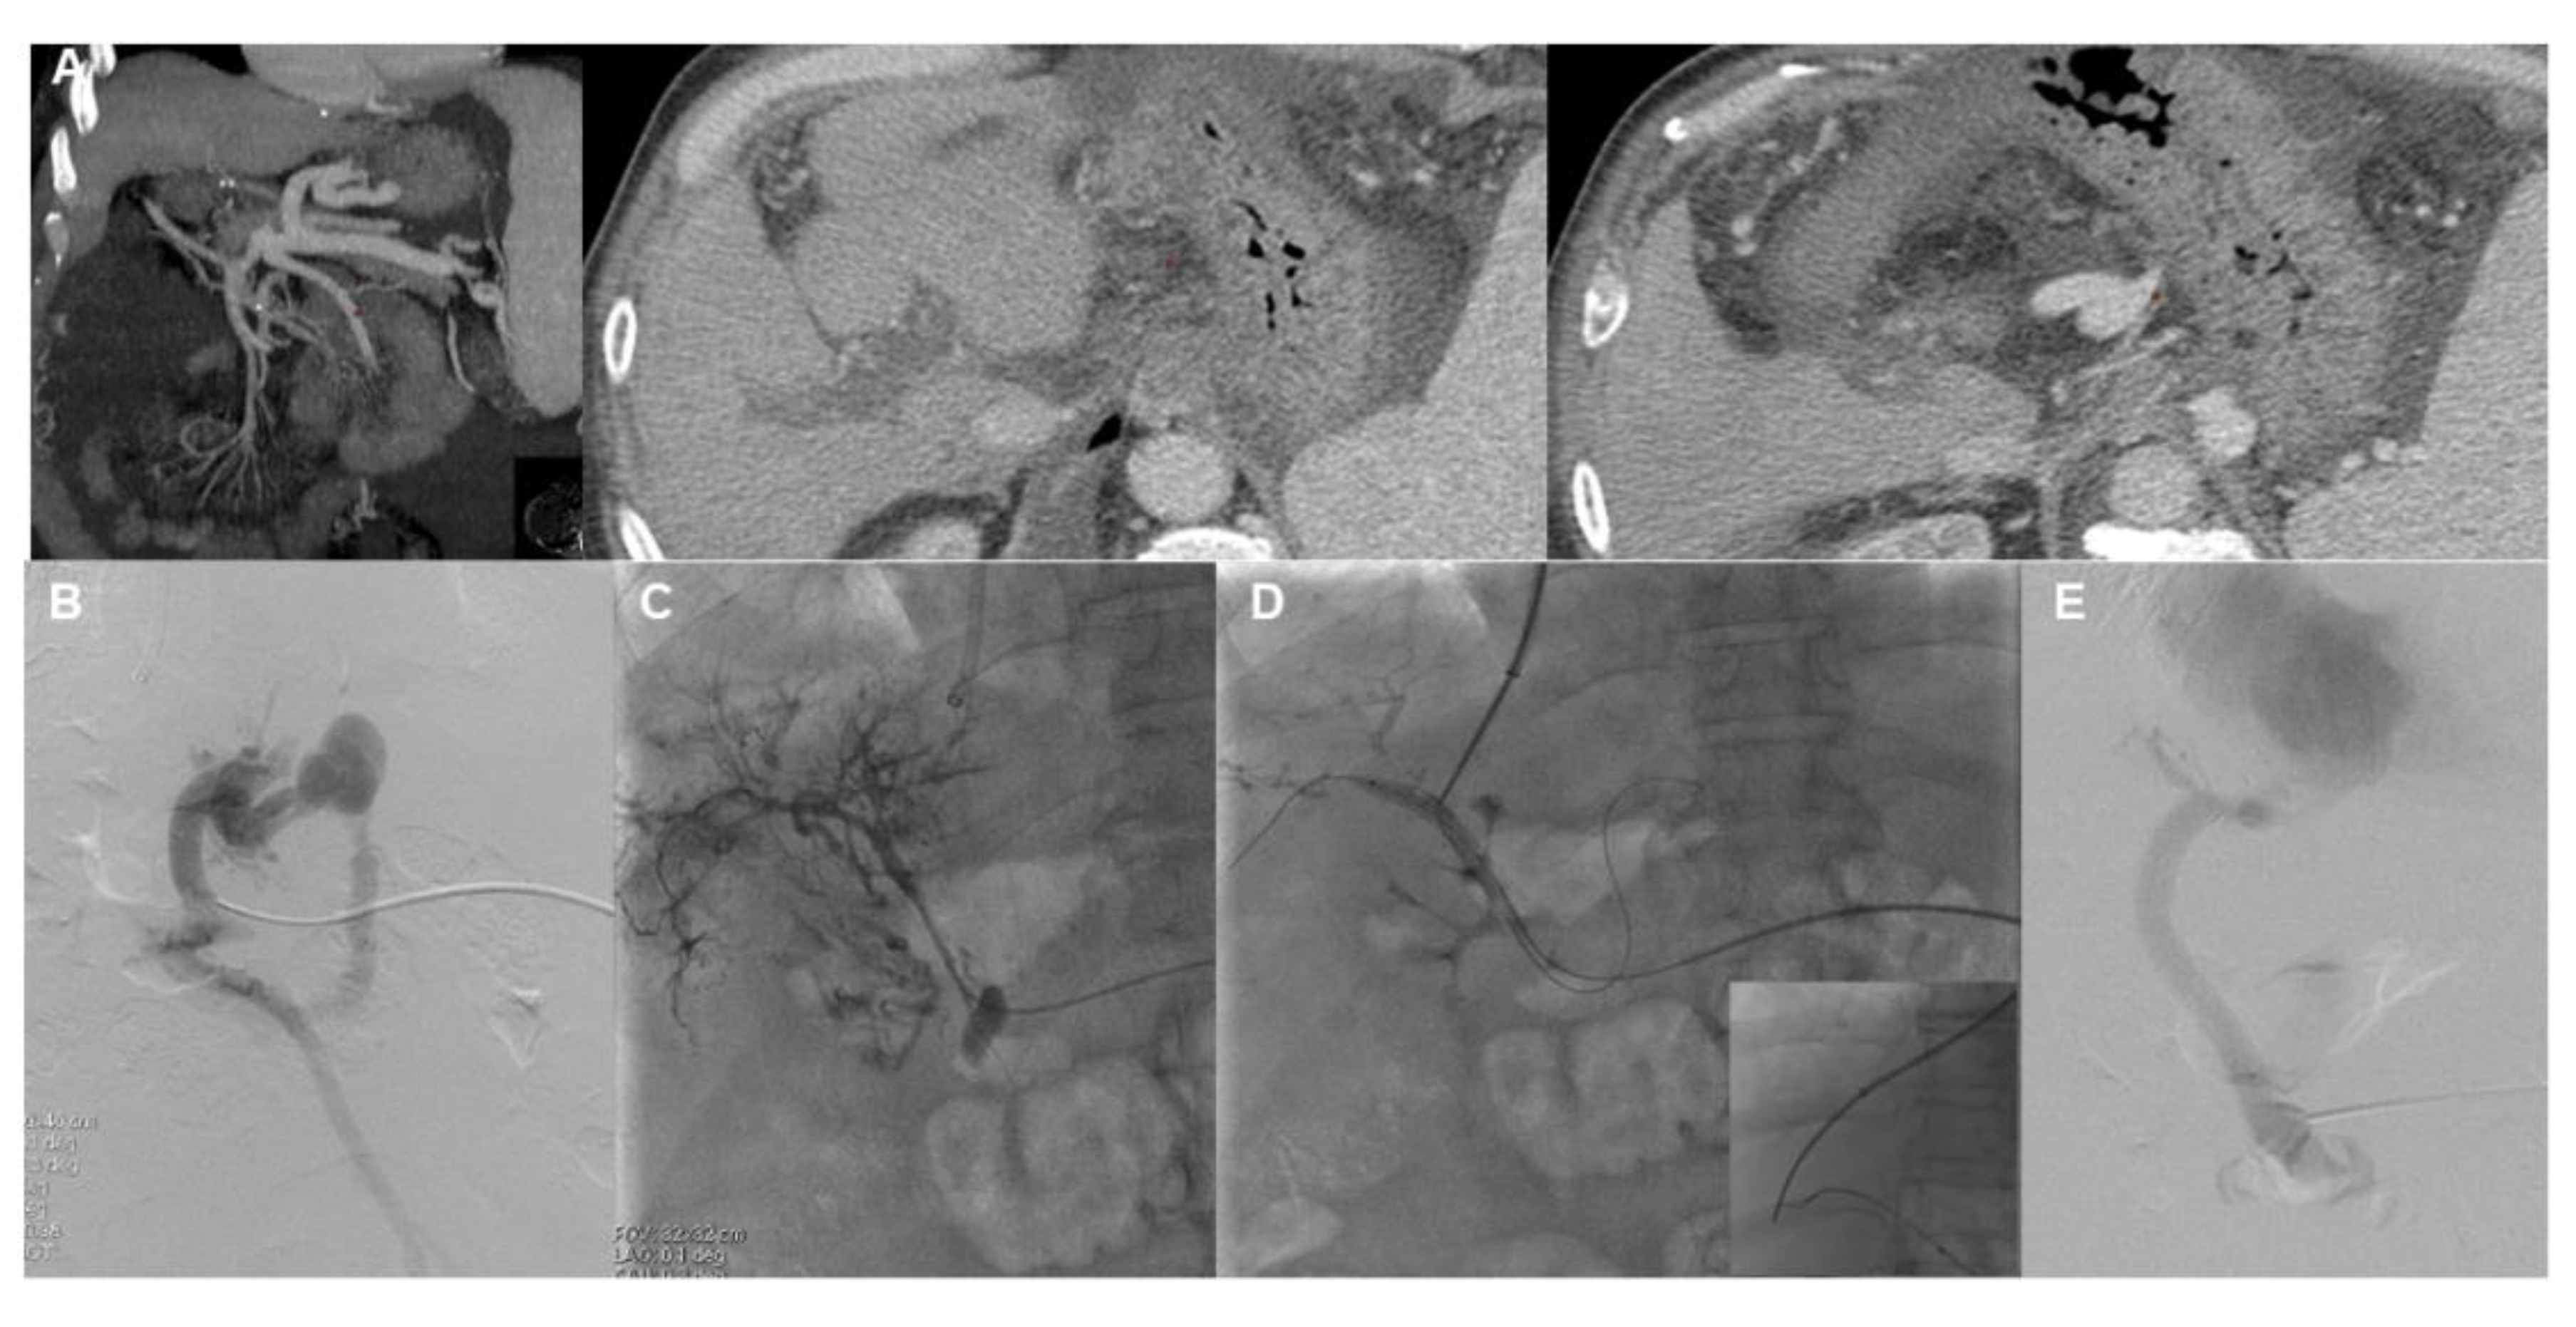

- Artru, F.; Vietti-Violi, N.; Sempoux, C.; Vieira Barbosa, J.; Becce, F.; Sah, N.; Marot, A.; Deltenre, P.; Moschouri, E.; Fraga, M.; et al. Portal vein recanalisation alone to treat severe portal hypertension in non-cirrhotic patients with chronic extrahepatic portal vein obstruction. JHEP Rep. 2022, 4, 100511. [Google Scholar] [CrossRef]

- Marot, A.; Barbosa, J.V.; Duran, R.; Deltenre, P.; Denys, A. Percutaneous portal vein recanalization using self-expandable nitinol stents in patients with non-cirrhotic non-tumoral portal vein occlusion. Diagn. Interv. Imaging 2019, 100, 147–156. [Google Scholar] [CrossRef] [PubMed]

- Chen, Y.; Ye, P.; Li, Y.; Ma, S.; Zhao, J.; Zeng, Q. Percutaneous transhepatic balloon-assisted transjugular intrahepatic portosystemic shunt for chronic, totally occluded, portal vein thrombosis with symptomatic portal hypertension: Procedure technique, safety, and clinical applications. Eur. Radiol. 2015, 25, 3431–3437. [Google Scholar] [CrossRef]

- Entezari, P.; Riaz, A.; Thornburg, B.; Salem, R. Percutaneous Ultrasound-Guided Superior and Inferior Mesenteric Vein Access for Portal Vein Recanalization-Transjugular Intrahepatic Portosystemic Shunt: A Case Series. Cardiovasc. Intervent. Radiol. 2021, 44, 496–499. [Google Scholar] [CrossRef]

- Steffen, D.A.; Najafi, A.; Binkert, C.A. Safety of Percutaneous Transmesenteric and Transsplenic Access for Portosystemic Shunt Creation in Patients with Portal Vein Obstruction: Single-Center Experience and Review of Literature. Cardiovasc. Intervent. Radiol. 2023, 46, 1401–1406. [Google Scholar] [CrossRef]

- Thornburg, B.; Desai, K.; Hickey, R.; Hohlastos, E.; Kulik, L.; Ganger, D.; Baker, T.; Abecassis, M.; Caicedo, J.C.; Ladner, D.; et al. Pretransplantation Portal Vein Recanalization and Transjugular Intrahepatic Portosystemic Shunt Creation for Chronic Portal Vein Thrombosis: Final Analysis of a 61-Patient Cohort. J. Vasc. Interv. Radiol. 2017, 28, 1714–1721. [Google Scholar] [CrossRef]